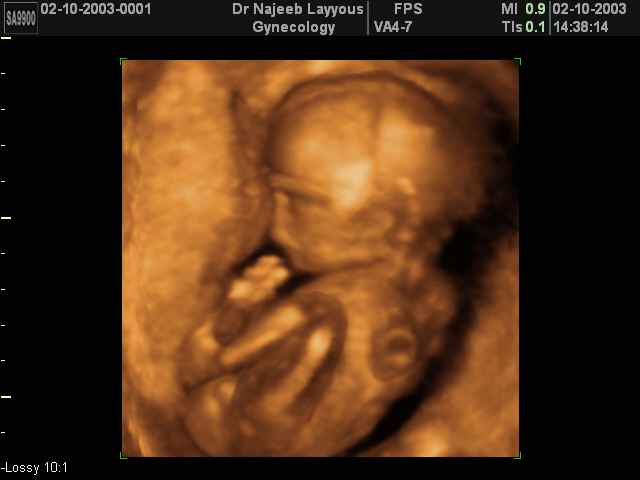

3D second trimestre échographie Photos de numérisation - deuxième partie de la grossesse | Dr N Layyous

3D second trimestre échographie Photos de numérisation - deuxième partie de la grossesse